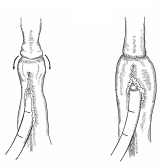

壁細胞。休止状態と分泌状態

どこかの国際学会でスライドに使っていただいたようです。確か一枚目を描くのに5時間、二枚目が3時間かかりました。